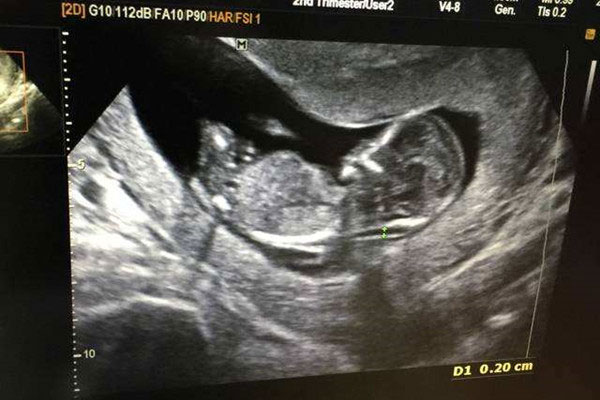

由于现在禁止胎儿性别鉴定,因此很多准父母试图从产检报告中看出胎儿性别,最近有流行一种nub点看男女的方法,主要是通过nub点与脊柱线的角度来判断胎儿是男是女。但是很多..

nt检查如何看男女?通过nub点看男女准确率高吗?

nt检查如何看男女?通过nub点看男女准确率高吗?nub又叫nubtheory,指的是胎儿的生殖节,nub最早出现在英国,因为很多人都认为nub可以准确的判断出胎儿的性别,所以在母亲..

产检nt彩超单子显示胎儿性别的nub点在哪?

通常nt彩超单子显示胎儿性别的nub都在胎儿的臀部处,如果大家能够在胎儿的臀部处能够看见一个像小尾巴样的东西凸出,我们就能准确的判断nub点的位置。虽然我们能够找到nub..